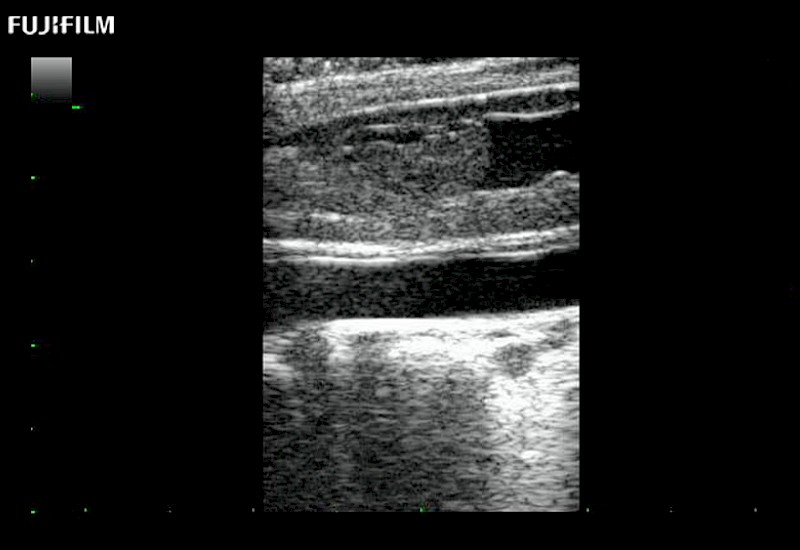

Tight curved (12mm) array transducer that is ideal for scanning during cranial guidance procedures.

Smaller footprint (20mm) curved array transducer that is ideal for scanning during cranial guidance procedures.

Hockey-stick linear array transducer is the transducer of choice for cervical spine scanning.